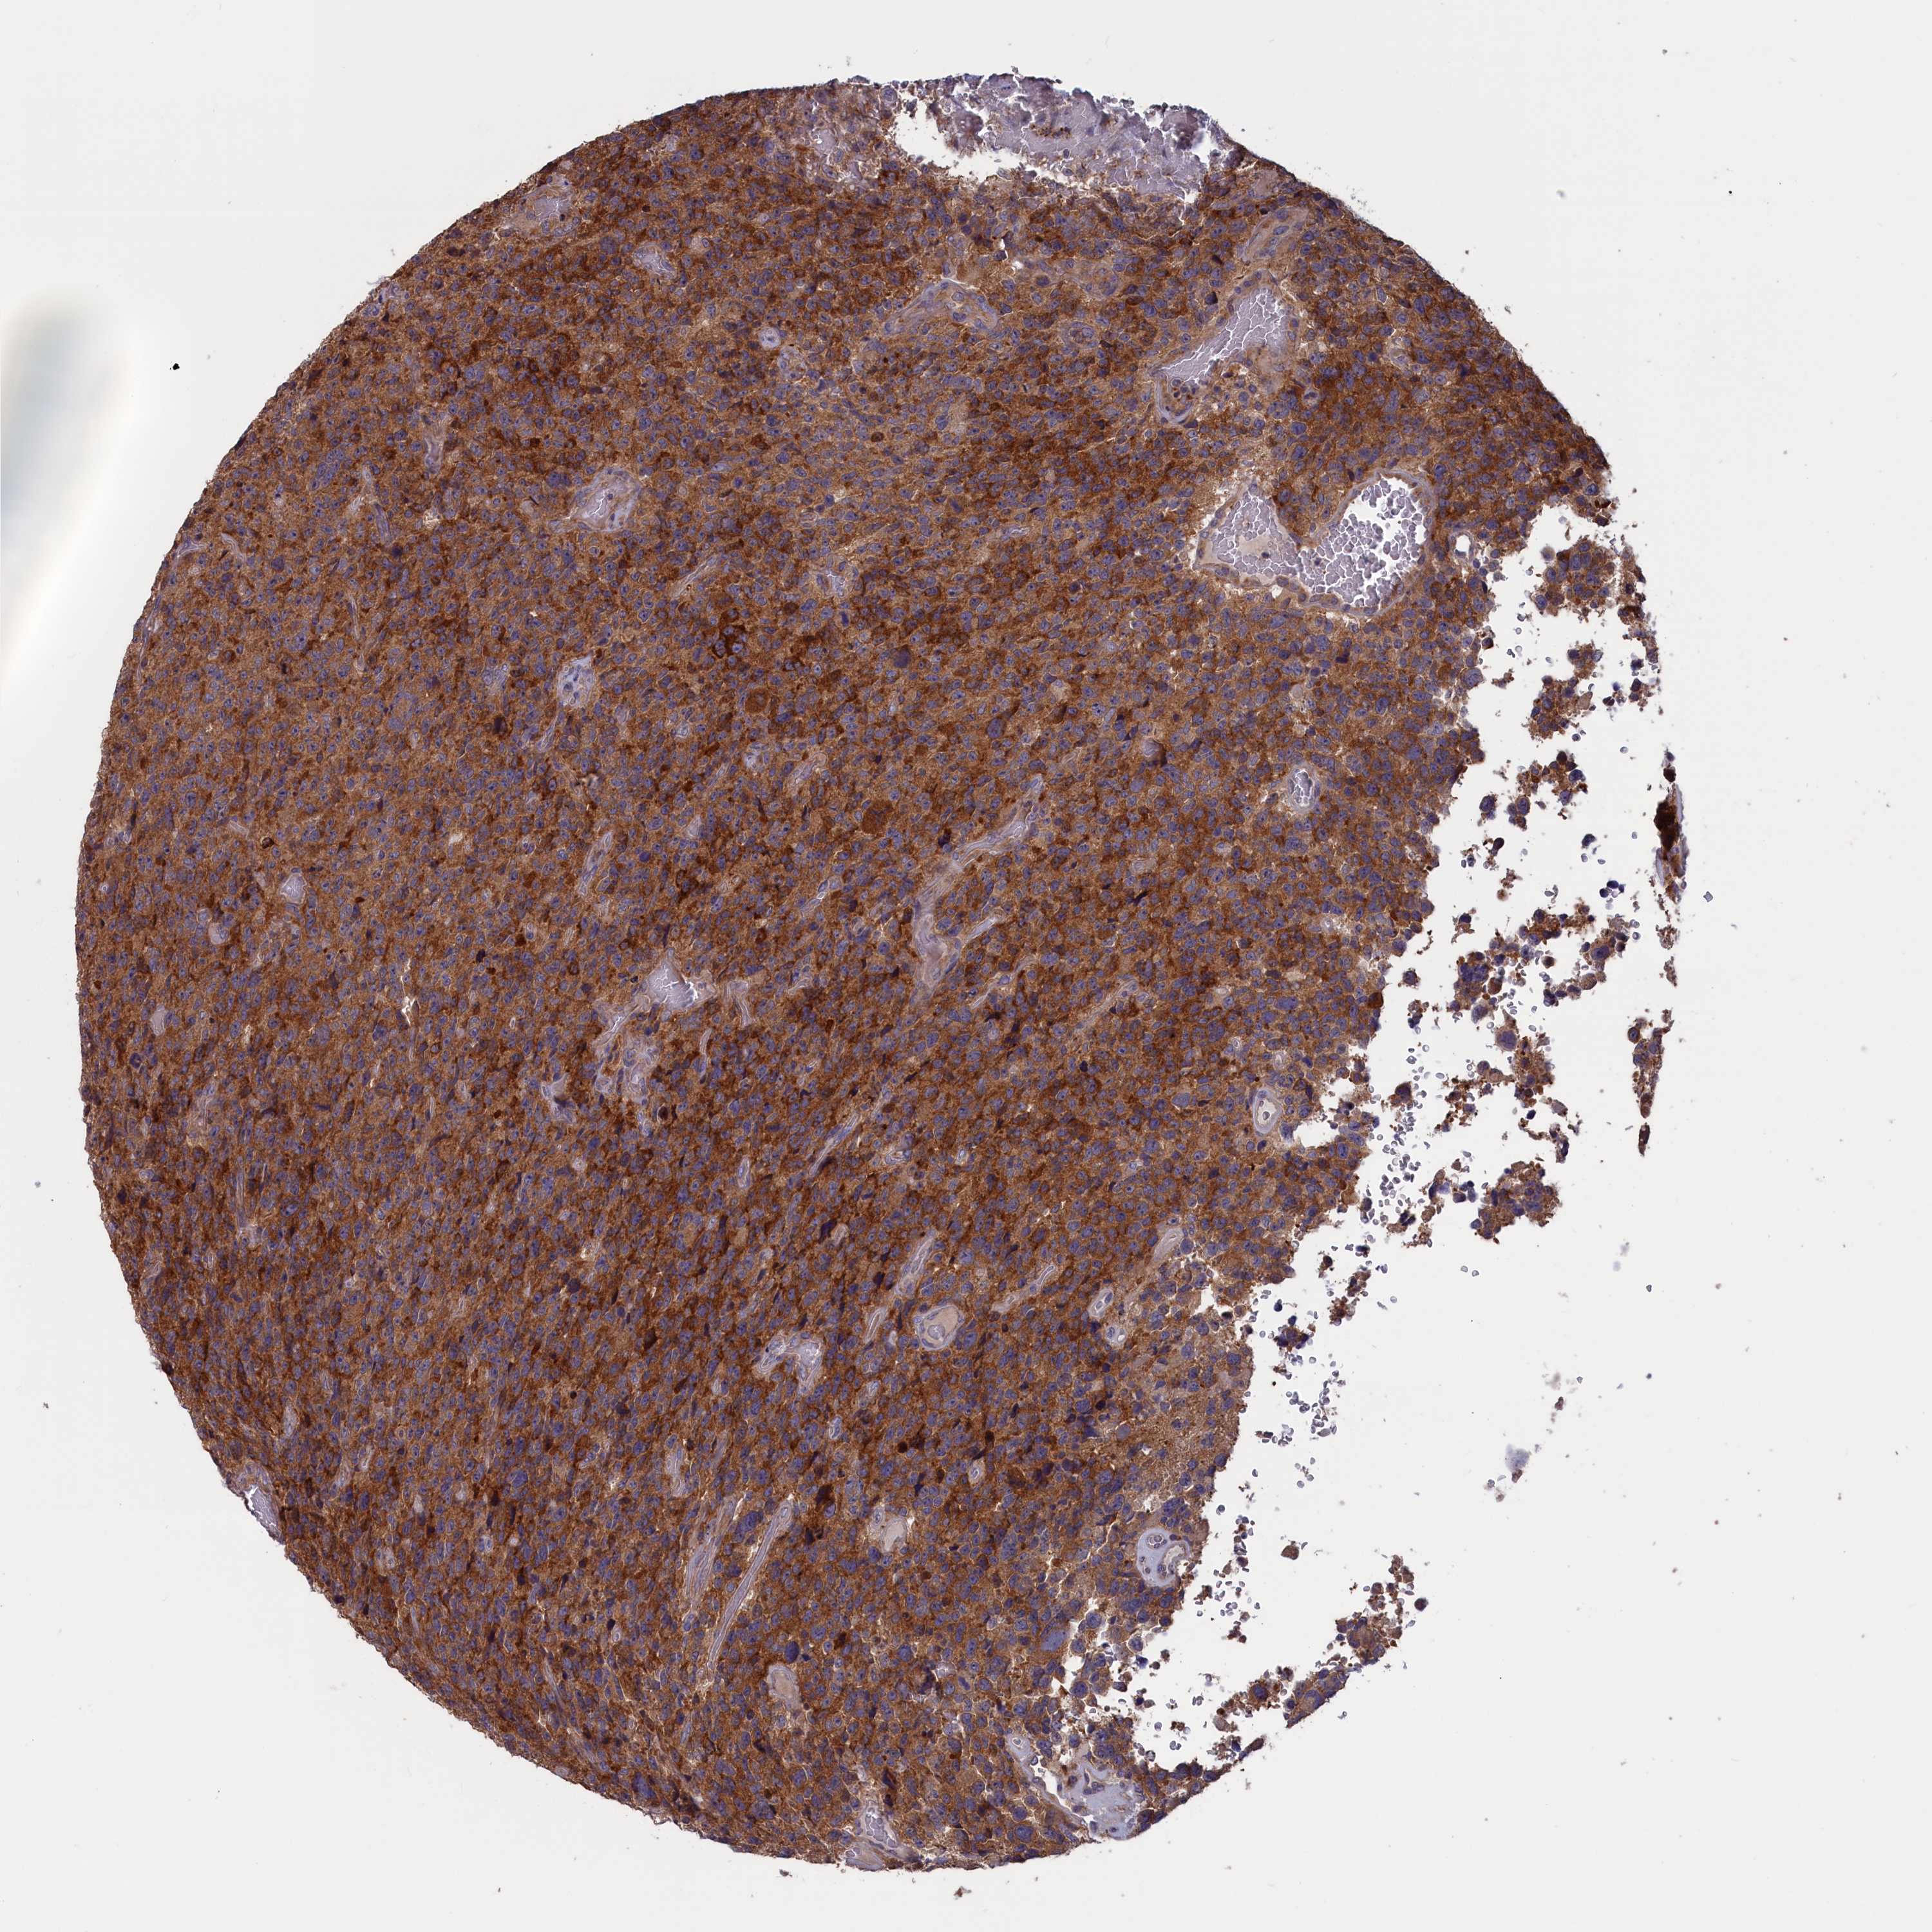

GLIOMA - Protein expressioni

A mouse-over function shows sample information and annotation data. Click on an image to view it in a full screen mode. Samples can be filtered based on level of antibody staining by selecting one or several of the following categories: high, medium, low and not detected. The assay and annotation is described here.

Note that samples used for immunohistochemistry by the Human Protein Atlas do not correspond to samples in the TCGA dataset.

Antibody stainingi

Antibody staining in the annotated cell types in the current human tissue is reported as not detected, low, medium, or high, based on conventional immunohistochemistry profiling in selected tissues. This score is based on the combination of the staining intensity and fraction of stained cells.

Each image is clickable and will lead to virtual microscopy that enables deeper exploration of all samples and also displays staining intensity scores, fraction scores and subcellular localization as well as patient and tissue information for each sample.

Antibody HPA042504

Antibody HPA042548

Staining

High

Medium

Low

Not detected

Intensity

Strong

Moderate

Weak

Negative

Quantity

>75%

75%-25%

<25%

None

Location

Nuclear

Cytoplasmic/membranous

Cytoplasmic/membranous,nuclear

Glioma, malignant, High grade

Glioblastoma, NOS